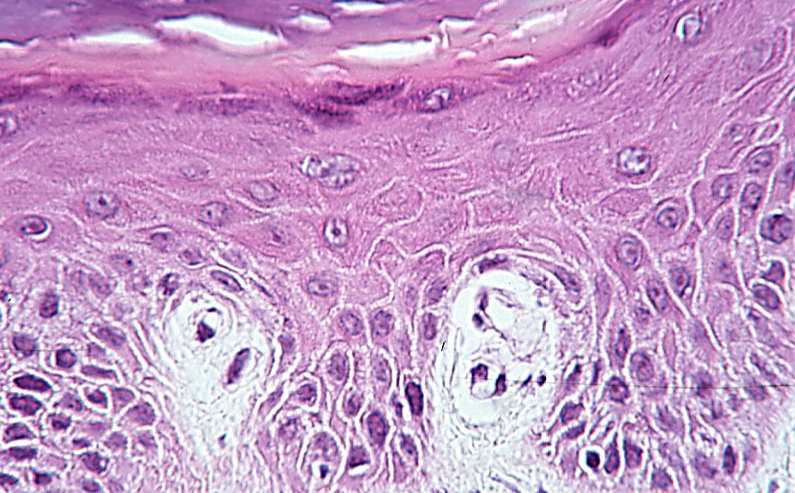

Thick Light Skin = جلد سميك وفاتح